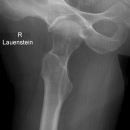

Hüfte axial (Sven Johansson)

Indikation

Cave: selten isoliert, meißt mit Luxation oder Azetabulum# kombiniert), Hüftgelenksluxation

Beurteilungskriterien

- Spongiosaarchitektur, Trajektorienverlauf im Schenkelhals (Cave: Bei nicht dislozierten SHF Diskontinuität der Trabekel oft einziges Frakturzeichen) Stellungsbeurteilung bei Schenkelhalsfrakturen oder Luxationen

- Gelenkstellung, Gelenkspaltweite, Luxation => Hüftkopf in zwei Ebenen im Azetabulum zentriert? Hüftkopfrundung?

- Trochanter major et minor (Abriss, pertrochantäre #?)

- med. Schenkelhalsfrakturen nach Pauwels I-III und nach Garden I-IV (2)

- SHF und Pertrochantere Frakturen AO-Klassifikation

- Hüftgelenksluxation Hüftkopffrakturen nach Pipkin

- Einteilung der medialen Schenkelhalsfrakturen nach Pauwels:

Pauwels I°: Winkel zwischen Horizontalen und Frakturlinie < 30°

Pauwels II°: zwischen 30° – 70°

Pauwels III° : > 70°